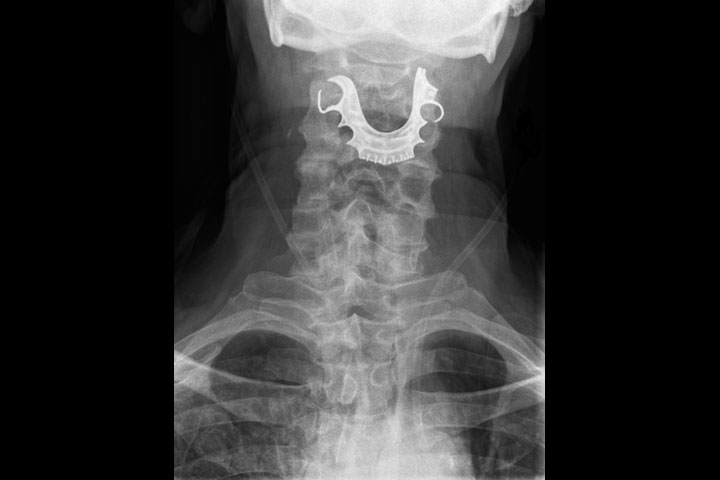

A neck X-ray showing a man’s dentures caught in his throat. BMJ Case Reports